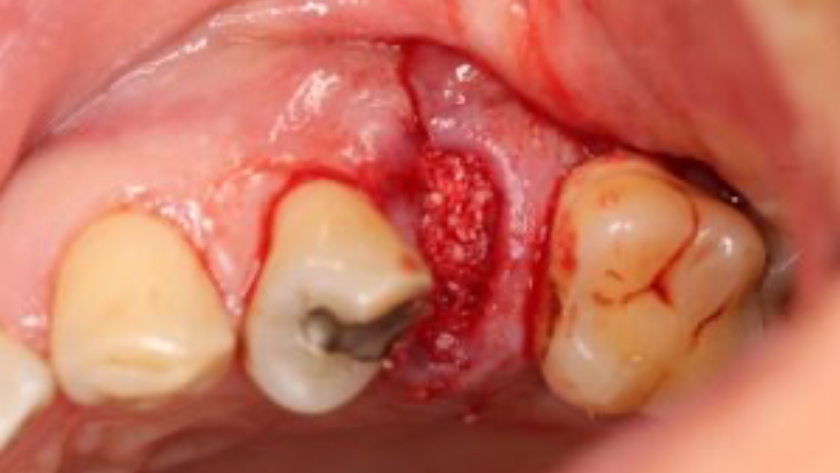

CLINICAL CASE

THE SITUATION

Tooth 13* required extraction in a 54-year-old male patient. The buccal bone was absent. Goal was to restore the site with an implant.